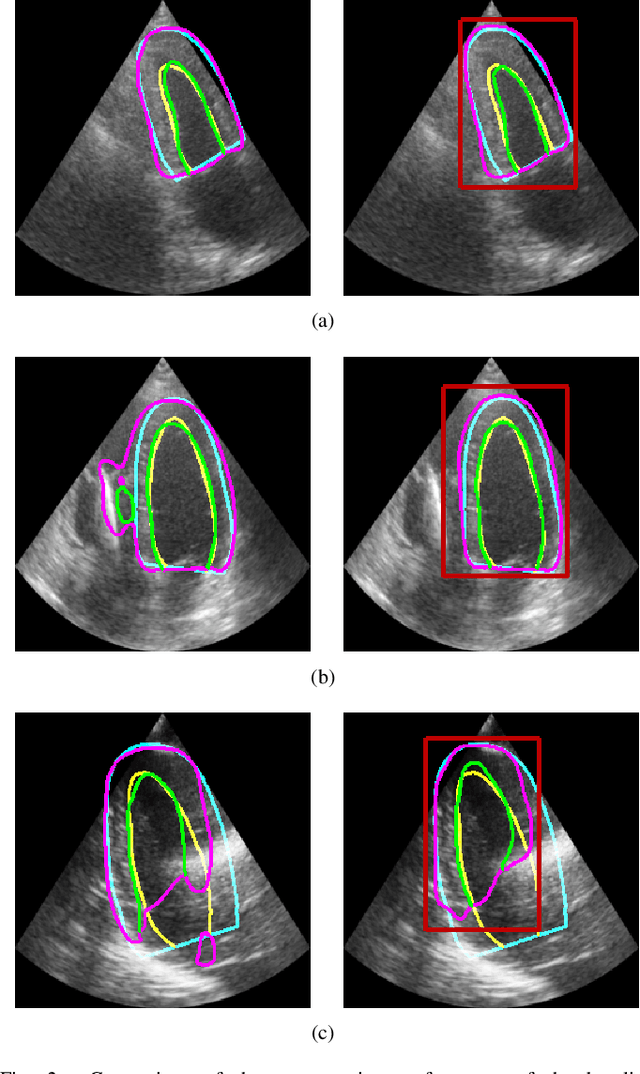

Abstract:Fully automatic cardiac segmentation can be a fast and reproducible method to extract clinical measurements from an echocardiography examination. The U-Net architecture is the current state-of-the-art deep learning architecture for medical segmentation and can segment cardiac structures in real-time with average errors comparable to inter-observer variability. However, this architecture still generates large outliers that are often anatomically incorrect. This work uses the concept of graph convolutional neural networks that predict the contour points of the structures of interest instead of labeling each pixel. We propose a graph architecture that uses two convolutional rings based on cardiac anatomy and show that this eliminates anatomical incorrect multi-structure segmentations on the publicly available CAMUS dataset. Additionally, this work contributes with an ablation study on the graph convolutional architecture and an evaluation of clinical measurements on the clinical HUNT4 dataset. Finally, we propose to use the inter-model agreement of the U-Net and the graph network as a predictor of both the input and segmentation quality. We show this predictor can detect out-of-distribution and unsuitable input images in real-time. Source code is available online: https://github.com/gillesvntnu/GCN_multistructure